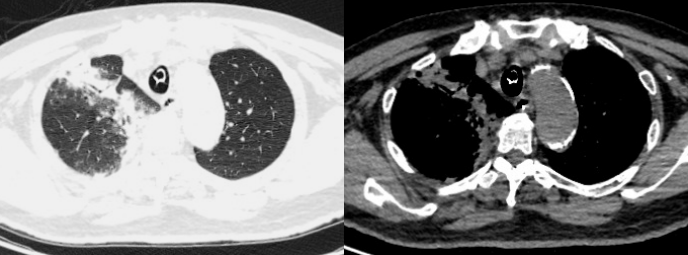

胸部CT(2025-04-23):右肺中上叶渗出,部分实变。右主支气管及右肺上叶支气管内多发黏液栓形成;两肺多发索条影;纵隔内稍大淋巴结;主动脉、冠状动脉硬化(图1)

1  患者入院胸部CT2025-04-23)